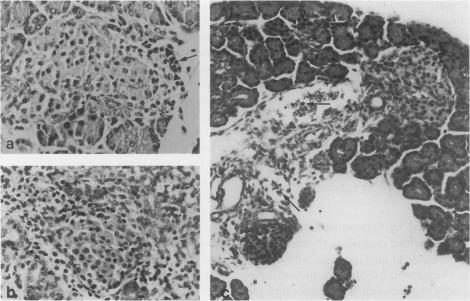

Reovirus type 2-induced diabetes-like syndrome in suckling mice is considered to be an animal model for human insulin-dependent diabetes mellitus. We have previously demonstrated that immunopathologic pancreatic islet cell damage might be relevant to reovirus type 2 infection. In this study the involvement of adhesion molecules in the development of reovirus type 2-induced diabetes-like syndrome was examined. In infected mice infiltration of mononuclear cells mixed with polymorphonuclear leucocytes in and around pancreatic islets (insulitis) was observed in association with abnormal glucose tolerance. The treatment with monoclonal antibodies against intercellular adhesion molecule-1 (ICAM-1) and lymphocyte function-associated antigen-1 (LFA-1) prevented the development of insulitis with abnormal glucose tolerance in a dose dependent manner. These results suggest that ICAM-1 and LFA-1 molecules may, at least in part, participate in islet cell damage, resulting in reovirus type 2-induced diabetes-like syndrome. The role of ICAM-1 and LFA-1 molecules on the development of insulitis is discussed.